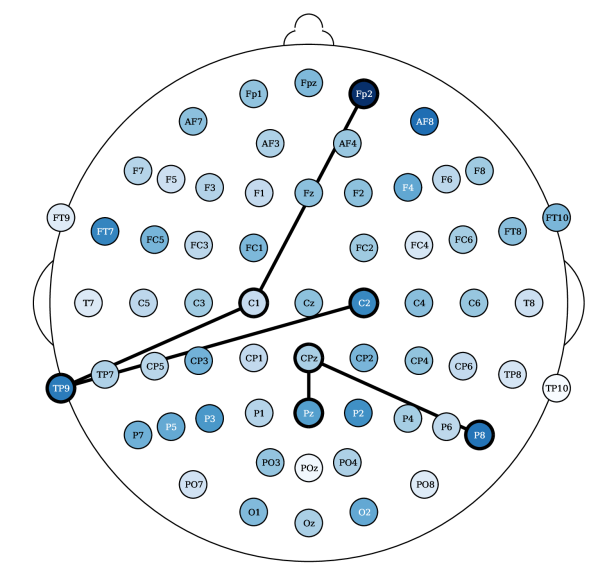

Most relevant electrode relations. Consider the relevance of the attention scores, computed from models (ii) and (iv), both having topographical attention at the EEG channel dimension, and model (iv) with projected random Fourier features in the latent space. These relevances were propagated, using the LRP algorithm [36] described in Appendix 0.E, through the attention style based posterior. Figure 5 shows the relevances plotted in a white to blue scale, from less relevant to most relevant, respectively. The latter only shows the edges that are above the percentile. The presence of an edge between electrodes suggests that either this connection yields a Markovian property for the EEG instance or, otherwise, it is relevant to add fMRI style conditioned on these connections (recall from Section 3.2 that posterior conditions the latent EEG representation such that ). For resting state fMRI, both Figures 10(a) and 5(a) show connections of parietal and occipital channels (O2 electrode in Figure 10(a) and Pz electrode in Figure 5(a)) with frontal and central channels to be the most relevant (above the 99.7 percentile of relevance). Figure 10(a) reports an additional connection between the Oz and PO9 electrodes, a correspondence between an occipital and a parietal-occipital electrode, which is in accordance with connectivity observations reported by Rojas et al. [6]. There were no reported relevances for the electrodes (T) placed in the temporal regions for resting state settings. In contrast, in task-based fMRI synthesis, relevant relationships between temporal (FT9 and TP9) and frontal/central (Fp2 and C1/C2, respectively) electrodes were reported, see Figures 10(b) and 5(b). In both of these figures, connections between central and parietal electrodes were observed. Particularly, there were reported connections between Cz with Pz and CP5 and CP2 electrodes in Figure 10(b). And connections between Pz and P8 with CPz electrodes in Figure 5(b).

Laboratory setup impacts EEG to fMRI synthesis. The results show that it is more difficult, according to the RMSE metric, to synthesize task-based fMRI than resting state. This observation is in contrast with studies that report that resting state fMRI is inherently more complex than task based fMRI [37]. The SSIM metric, in contrast to the RMSE, shows less significant differences for the Oddball recordings in favor of fMRI synthesis in the resting state. However, the CN-EPFL dataset is not in accordance with the latter. This performance heterogeneity across the datasets may not only rise from the characteristics of the recording sessions, but may also be also propelled by the different preprocessing techniques employed. Each dataset is publicly available and is supported with published studies, having unique equipment, experimental protocols, and algorithms. CN-EPFL dataset is the most complete one, with a total of 20 individuals and with a resolution of mm, which makes a total of voxels. These differences, caused by working with 3 Tesla (CN-EPFL dataset) versus 1.5 Tesla (NODDI and Oddball datasets) scanners, significantly impact the spatial resolution, which for the datasets NODDI and Oddball produce and voxels, respectively, with around mm voxel size. One has to further account for the original recording artifacts and disruptions caused by the applied preprocessing techniques. For instance, Oddball dataset contains intra and inter individual wise misalignments across fMRI volumes. This may be the cause of poorer performance of all methods when compared to the other datasets. In addition, Oddball relies on a different EEG electrode positioning system, having a total of electodes that were not placed in accordance with the 10-20 system [26]. Although NODDI and CN-EPFL recordings are in accordance with this system, each selected unique electrode locations (see the different electrode placements between Figures 5(a) and 5(b)). Finally, the different EEG sampling frequencies, with Hz, Hz and Hz considered in NODDI, Oddball and CN-EPFL recordings, respectively, further affect architectural operations and subsequently impact the learning.